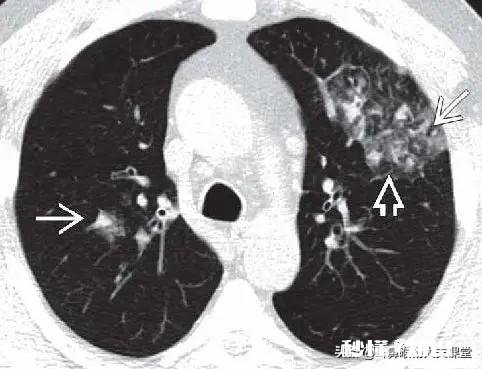

病毒性肺炎CT特点:

1. 常有磨玻璃影;

2. 常有斑片状实变影;

3. 重症患者病灶常多发;

4. 部分间质性改变;

5. 病灶进展迅雷不及掩耳之势;

6. 几乎不会形成空洞,除非合并细菌感染等情况;

7. 一般少有胸腔积液,就算是有,几乎都是少量胸水 , 中大量胸水估计是合并其他疾?。?

8. 典型特点,病变早期 , 分布于胸膜下或支气管血管周围的类圆形磨玻璃影 。